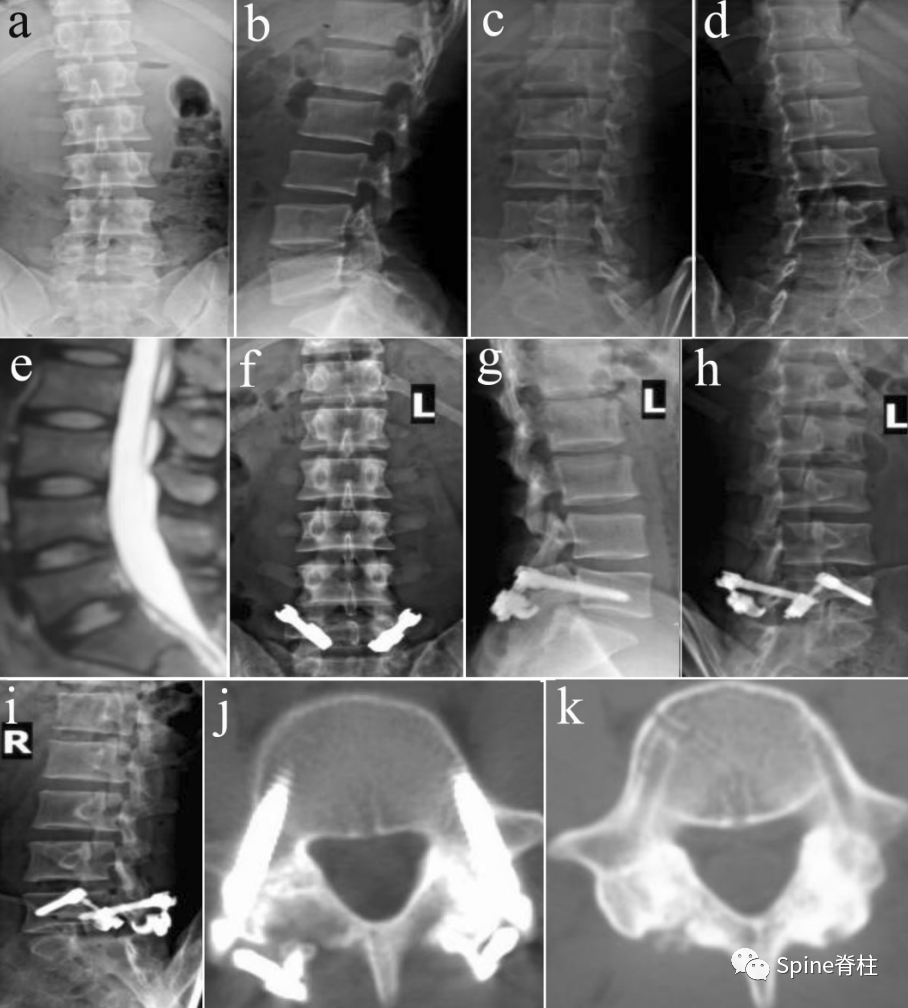

2019年国内解放军总医院第七医学中心李放教授团队。根据临床特点和影像学表现将所有病例分为3型:

• A型为单纯型峡部裂,无椎间盘突出及腰椎滑脱;

• B型为峡部裂伴有轻度椎间盘突出或I度滑脱,无神经压迫症状及体征;

• C型为峡部裂合并I度或Ⅱ度滑脱并椎间盘突出同时有神经压迫症状及体征。

并建议保守治疗无效的青年战士A、B型腰椎峡部裂病例采用椎弓根螺钉固定,峡部自体髂骨原位植骨融合率高,效果好,C型战士峡部裂则宜采用后路椎间植骨融合椎弓根螺钉内固定术。